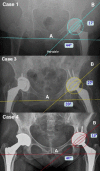

Dislodgment of trial femoral heads and migration into the pelvis during total hip arthroplasty is a rarely reported complication with limited published cases. There are three primary mechanisms of femoral head separation: dislodgement during reduction attempt, disassociation from anterior dislocation while assessing anterior stability, and during dislocation after implant trialing. If the trial femoral migrates beyond the pelvic brim, it is safer to finish the total hip arthroplasty and address the retained object after repositioning or in a planned second procedure with a general surgeon. We recommend operative retrieval since long-term complications from retention or clinical results are lacking.